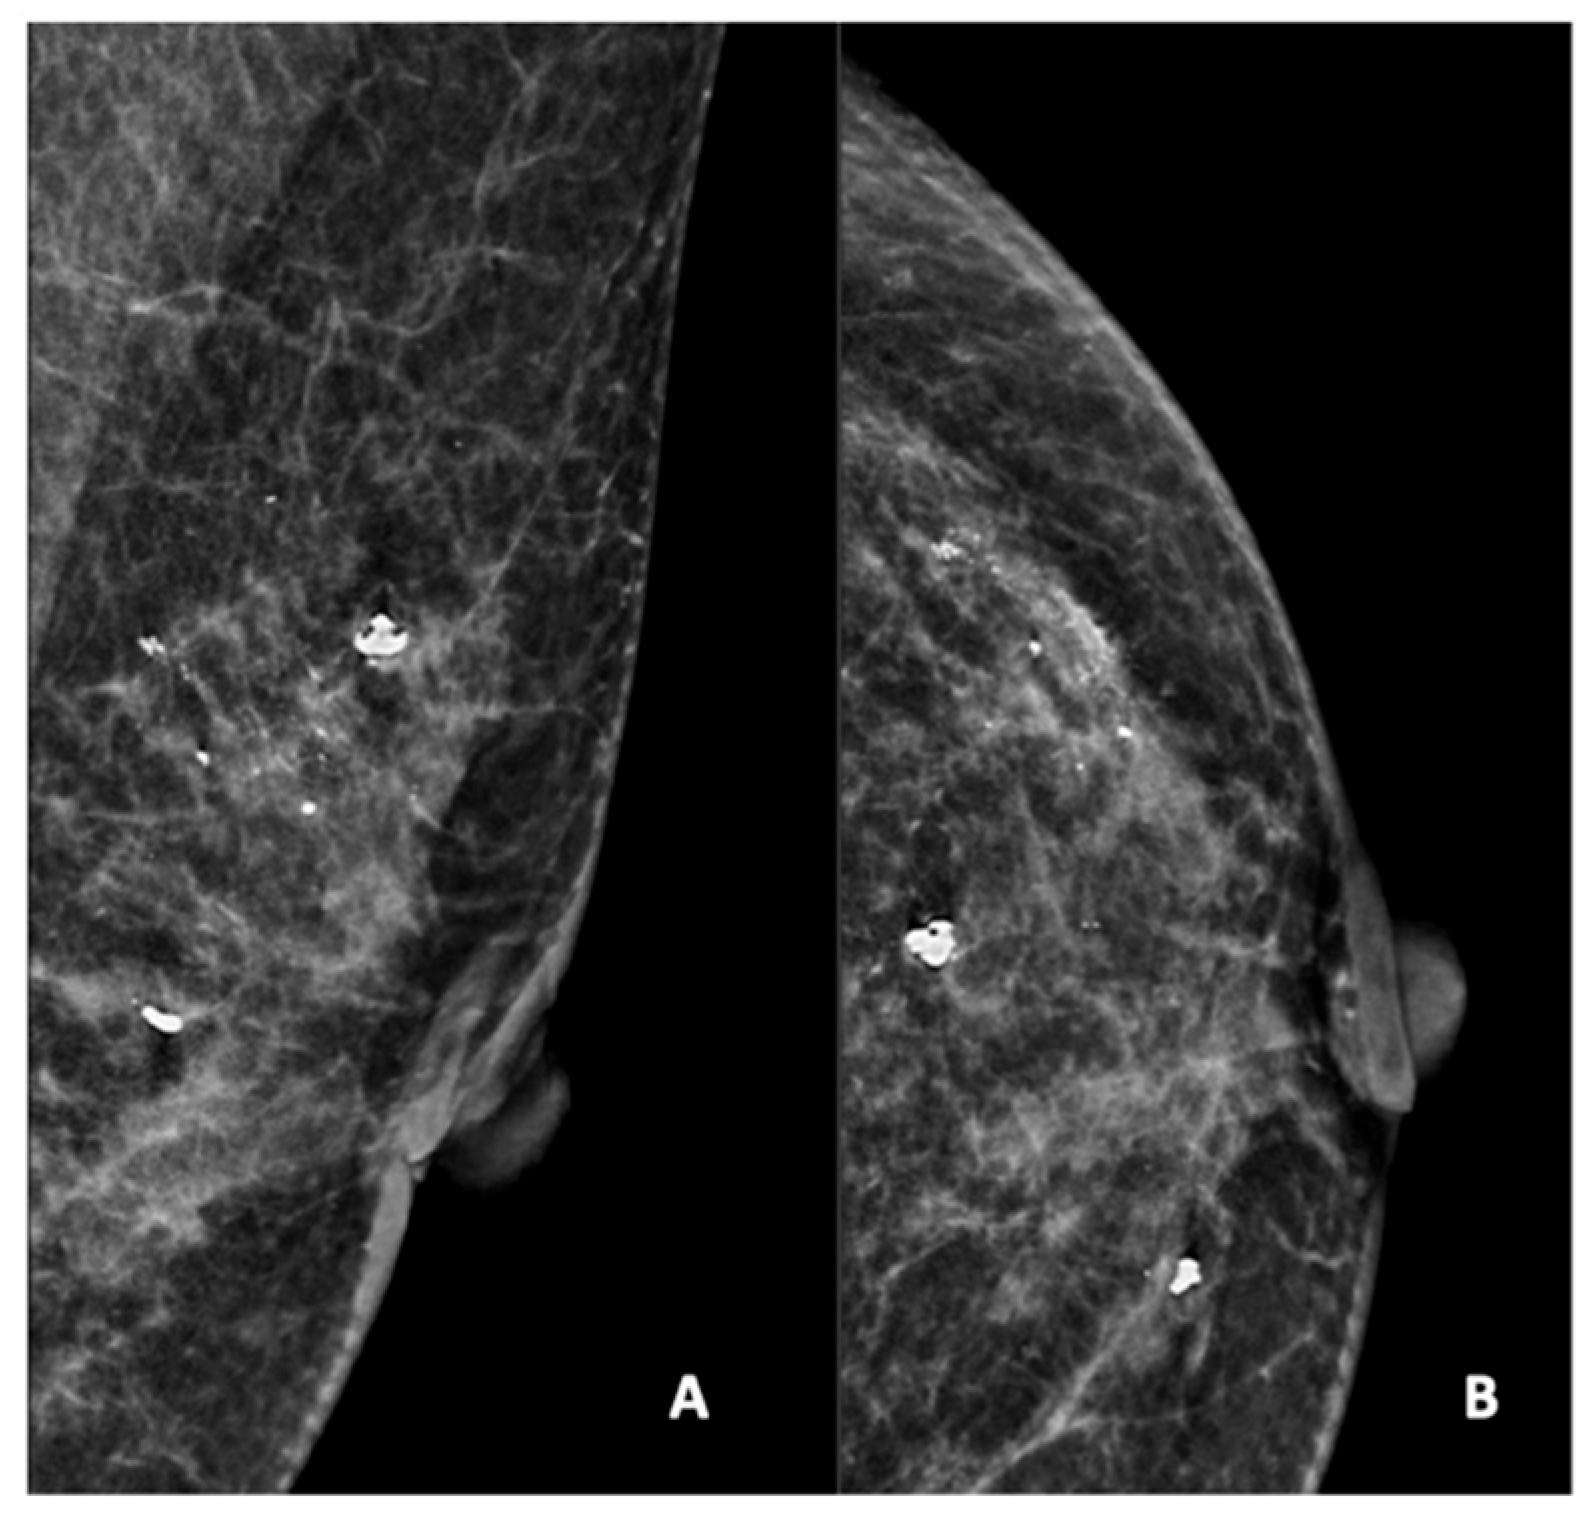

Figure 2.

Mammogram study of a left breast in (A) mediolateral (MLO) view and (B) craniocaudal (CC) view, showing amorphous calcifications in a segmental distribution in the upper outer quadrant, reported as a BI-RADS 4 lesion. Given these calcifications, a stereotactic-guided core biopsy was performed; the HPE showed DCIS. There were also benign coarse calcifications in the upper outer and mid-inner quadrants.